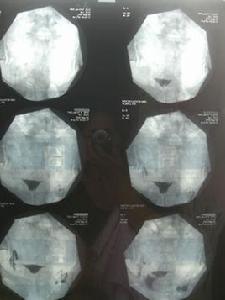

若結石卡在輸尿管上段時,疼痛會在腰及上腹部,甚至傳到睪丸或外陰部;在中段時,疼痛通常在腰及下腹部;若在下端接近膀胱處時,疼痛除了在腰及小腹外,有時也會引起頻尿、小便困難或解不出的症狀。

結石可刺激、擦傷輸尿管黏膜,以致出血,並發感染,致使輸尿管擴張,管壁變薄,伸長彎曲更為嚴重;結石嵌頓處的輸尿管由於炎變致使組織增生而纖維化,輸尿管變厚。但結石穿破輸尿管的病例則極少。不孕不育專家介紹說,梗阻引起不同程度的腎積水,損害腎實質,並發感染,還可發生腎盂腎炎、腎膿腫。

在輸尿管中、上段部位的結石嵌頓堵塞或結石在下移過程中,常引起典型的患側腎絞痛和鏡下血尿。疼痛可向大腿內側、睪丸或陰唇放射。常伴有噁心、嘔吐,有時血尿為肉眼可見。輸尿管膀胱壁間段最為狹小,結石容易停留。

輸卵管結石的危害由包括由於輸尿管下段的肌肉和膀胱三角區相連,並且直接附著於後尿道,故常伴發尿頻、尿急和尿痛的特有症狀。在不影響尿流通過的較大結石,可僅有隱痛,血尿也輕。在孤立腎的輸尿管結石阻塞或雙側輸尿管阻塞,或一側輸尿管結石阻塞使對側發生反射性無尿等情況,都可發生急性無尿,甚至腎功能不全。